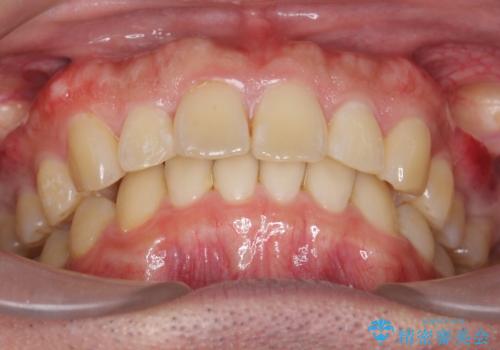

出っ歯を治したい 深いかみあわせ インビザラインで治療

上顎は歯を抜かずに、奥歯を後ろに下げる治療を行っています。

下顎は歯列を拡大して並べました。

歯を抜かずに奥歯を後ろに動かすために、矯正用のミニスクリューを使用しています。

また、過蓋咬合(深いかみ合わせ)で食いしばりがきつく、歯の移動には大変時間がかかりました。

食いしばりがきついかたについては、長時間マウスピースをはめると奥歯が咬まずに前歯に負担がかかる場合があります。今回は使用時間を短くしたり、下の歯並びを早めにプレートタイプリテーナーに置き換えるような工夫を行い、治療を行いました。